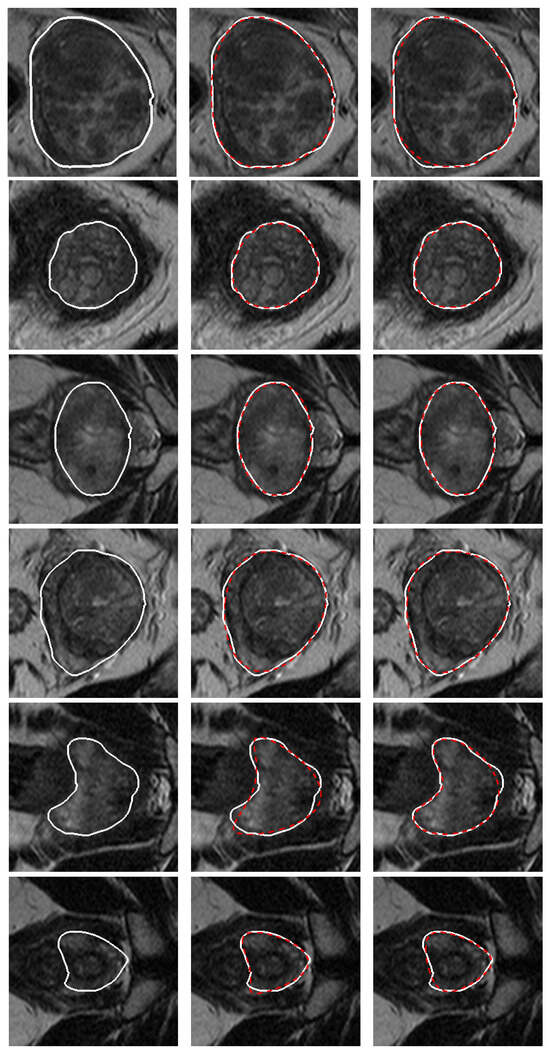

3. Validation of the Models

4. Results and Discussion